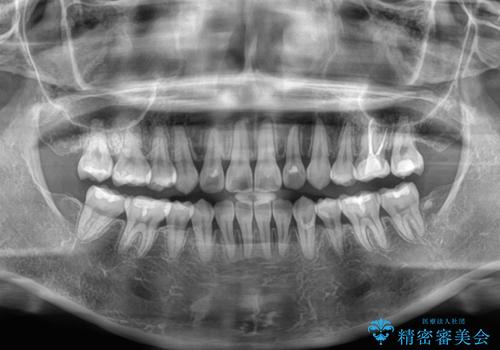

- 上下前歯の後戻りを気にして来院された患者様です。

インビザラインでの治療を希望されていて、デコボコの程度が中等度であり、安価なパッケージにて対応可能と判断されたため、インビザライン・モデレートを用いて矯正治療を行うこととしました。